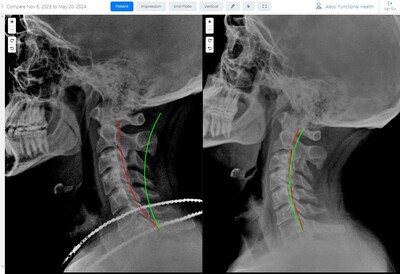

Results You Can See... and Feel!